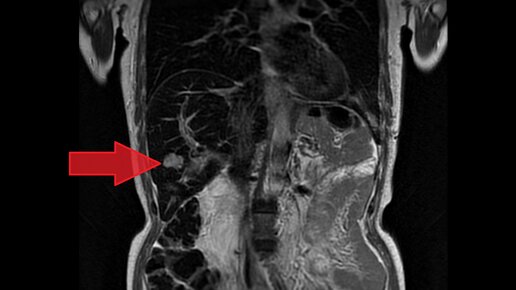

Пациентка И., 62 года. При обследовании в 2021 году выявлена опухоль головки поджелудочной железы с метастатическим поражением печени.  Выполнена биопсия опухоли, по данным гистологического исследования получен рост злокачественной опухоли - умереннодифференцированной протоковой аденокарциномы поджелудочной железы. При подобной распространенности заболевания единственной потенциально эффективной лечебной опцией является проведение системной лекарственной терапии. Операция не имеет смысла. В качестве первой линии назначена химиотерапия по схеме FOLFIRINOX...